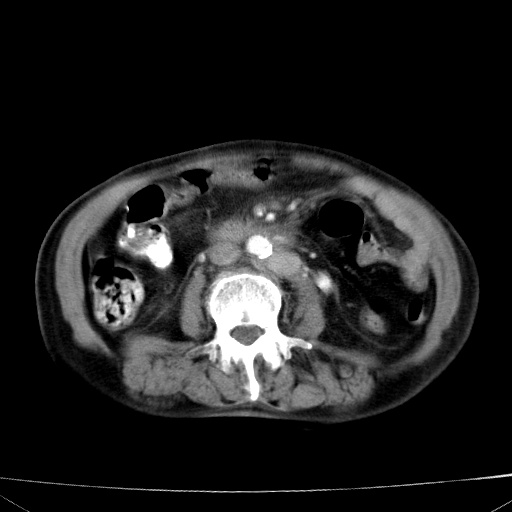

网站人气太旺!昨天的帖子就沉到海底,只好再发贴!ct18338:女 78岁,肝胆病变,已增强,再会诊!原帖链接:http://www.radida.com/bbs/forum.php?mod=viewthread&tid=50032

1)考虑胆囊癌侵犯肝脏并肝门区、腹膜后及右侧膈角后淋巴结转移。2)肝左叶近肝顶部囊肿。3)肝左叶肝内胆管结石。4)左肾近下极囊肿。

1)考虑胆囊癌侵犯肝脏并肝门区、腹膜后及右侧膈角后淋巴结转移。2)肝左叶近肝顶部囊肿。3)肝左叶肝内胆管结石。4)左肾近下极囊肿。支持